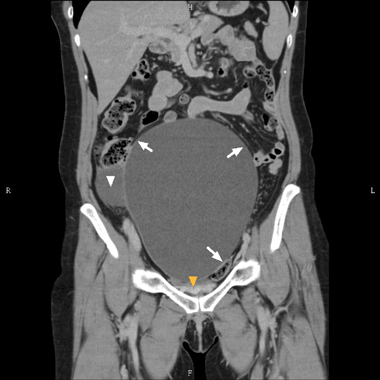

A 55-year-old woman, who had undergone a total hysterectomy decades previously, presented with lower abdominal fullness and urinary frequency. An abdominal–pelvic contrast-enhanced computed tomography scan (Box) showed a large cystic lesion measuring 20 × 17 × 15 cm, with a smaller “daughter” cyst, a compressed urinary bladder and bilateral hydronephrosis.

The patient subsequently had an ovarian cystic tumour weighing 1822 g removed, and had an uneventful postoperative course. The tumour contained serous fluid, which established the diagnosis of serous borderline ovarian tumour (SBOT). An SBOT manifesting as such a large cyst that mimics neurogenic bladder is rare.1 In general, conservative, fertility-sparing surgery is recommended for its promising outcomes.2